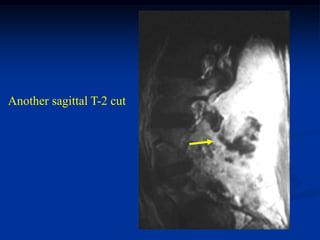

Case #1103

34 year male with

chordoma L-5

tumor

CT scan at L-5 shows chondroid like tumor arising from

the postero-lateral elements of L-5

Another CT cut

Another

Axial T-1 MRI

Axial T-2 MRI

Another axial T-2 MRI

Sagittal T-2 MRI

Another sagittal T-2 cut